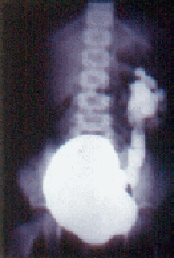

Figura 2. Divertículo parameatal sin reflujo.

En la Figura 2 vemos otro divertículo parameatal en una hembra de 4 años cuyo motivo de consulta igualmente fue una infección. Pero en este caso no hay reflujo. El divertículo era congénito, sin pared muscular, pero la unión ureterovesical se mantuvo y no permitió el reflujo. En esta niña no existía nefropatía detectable por urografía.